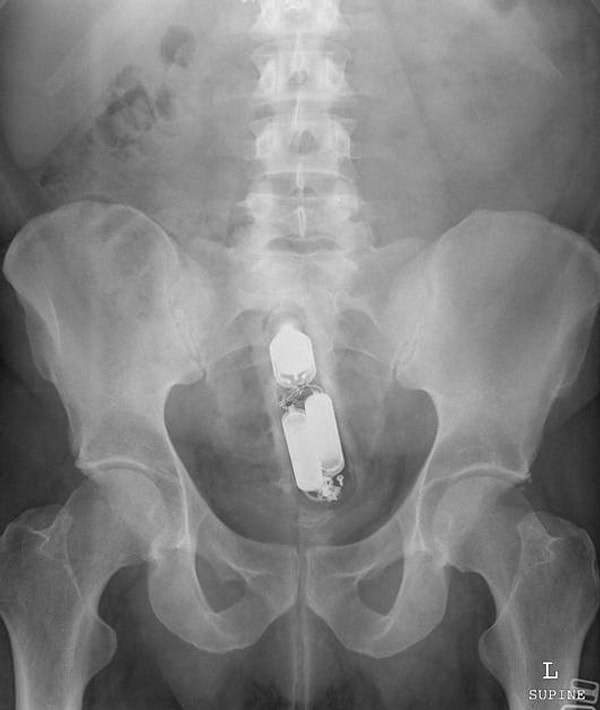

Итак, вашему вниманию предоставляются сами снимки. Попробуйте угадать, что там за предмет, если не сможете, то внизу есть подпись.

Аэрозольный баллончик.